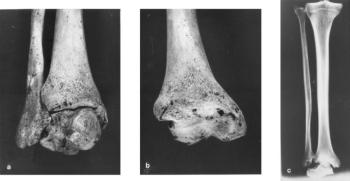

73. ábra. a) Az ugróízületet alkotó valamennyi csonton és ízfelszínen súlyos arthrosisos b) A tibia ugróízületi felszíne c) A felső ugróízületet képező csontok rtg képén kifejezett eburnificatio figyelhető meg 10–12. század, maturus férfi

Ostearthritisben az ízületi porc megvastagszik, tömött burjánzó göbök és kimaródások, mély berepedések, az ízület peremén osteophyták képződése, eburnifikálódás, a subchondralis csontkéreg kiszélesedése látható, gyakori a csont-porc határon elhelyezkedő, részben gyógyult microfractura, a subchondralis gerendázat feldúsulása, az osteophytákban fonatos csont képződése. Ezek a markáns eltérések mind makroszkóposan, mind a rtg-felvételeken jól látszanak (71. ábra, 72. ábra). Olykor a subarticularis szivacsos állományában cysták alakulnak ki, de osteopenia nem. A múmiákban (a fentieken kívül) az ízületi synovia megvastagodása, esetleg lobos beszűrődése, néha az ízület körüli bőrben Heberden csomók is kimutathatók (Alarcon-Segovia 1976). A tokban képződő porcszigetek (rizs-testek, vagy corpora oryzoidea) bejuthatnak az ízület üregébe.

74. ábra. Egyenlőtlen vastagságú, elmeszesedett porcréteg, vaskos corticalis az arthrosisos ugrócsontban (makroszkóposan lásd 73. képen) Pikrosziriusz festés. 100× nagyítás. a) fénymikroszkópos, b) polármikroszkópos felvétel

Másodlagosnak nevezik, amikor valamilyen biomechanikai hiba miatt egy ízületben, vagy egy végtag teherviselő ízületeiben alakul ki az OA. Rendszerint megállapítható a rossz helyzetű törésgyógyulás, esetleg az ízületi tengely megváltozása (X-láb és vagy gacsos térd). A veleszületett csípődysplasiához 20-30. év körül súlyos arthrosis társul. Előfordulhat, hogy a monoton, repetitiv mozgás csak egyetlen vagy a szimmetrikus (könyök) ízületeket terheli, s ilyenkor foglalkozási ártalomnak tekinthető (During és mtsai 1994). A másodlagos forma makroszkópos, mikroszkópos és röntgenmorfológiai képe mindenben megegyezik a primer osteoarthritisével (73. ábra, 74. ábra).